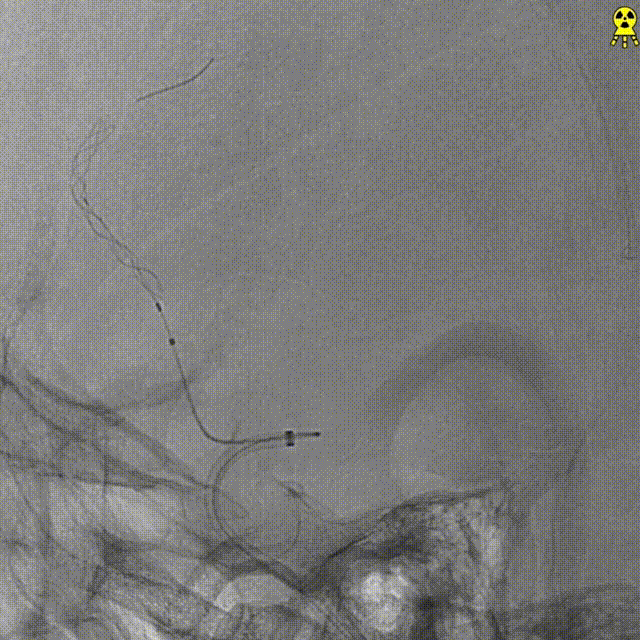

微导管到位。

交换FLOPPY导丝,提高支撑力,带高中间导管。

输送球囊到位、充盈及泄压。

撤出球囊后造影。

支架微导管到位。

支架到位。

支架全段打开。

支架全段打开造影。